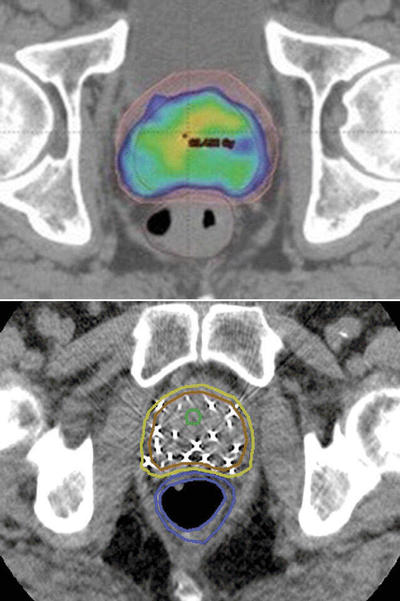

前立腺がん放射線治療

朝日大学病院放射線治療医田中修氏今回は、前立腺がんの治療についてです。方法としては手術、抗がん剤、そして、放射線治療があります。まず手術に関しては最近、ロボット手術の普及もあって傷跡が小さくなり...